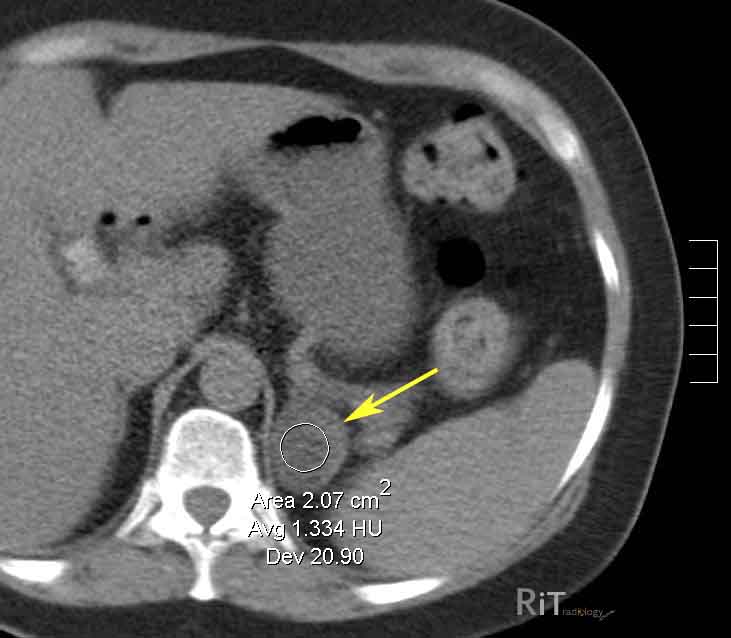

Плотность и здоровье надпочечников на КТ